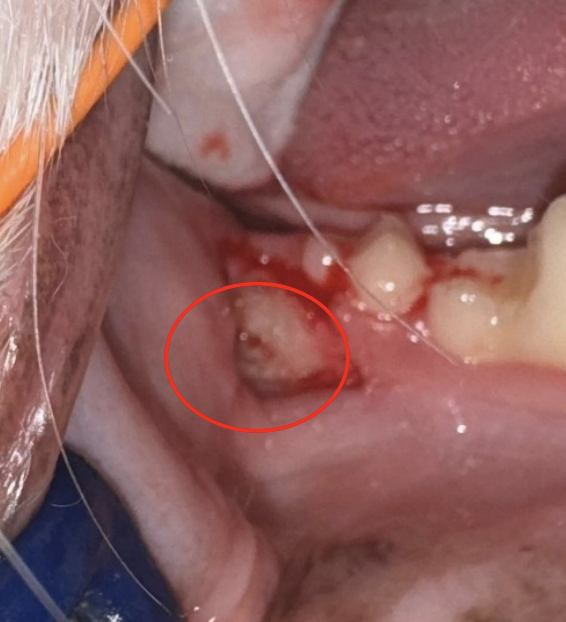

▲ 埋伏歯 抜歯後

▲ 抜歯後に歯肉縫合

埋伏歯は抜歯を行い、歯肉は縫合を行いました。

縫合の糸は、髪の毛よりも細い糸を使用しております。また、縫合糸は数ヶ月で溶ける糸を使用するため、基本的には抜糸の必要がありません。